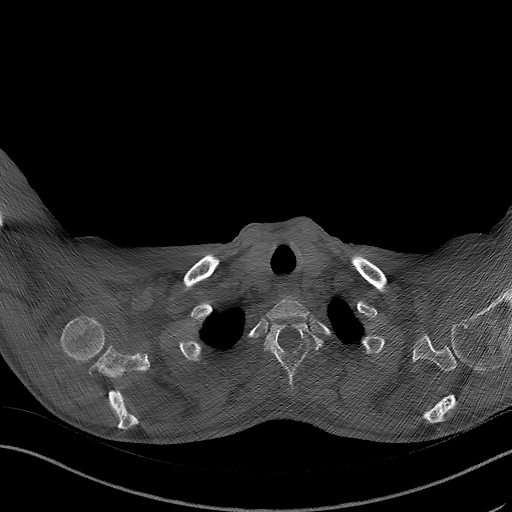

For the BM segmentation task, we compared the predicted masks generated by our approach with those from three competitive methods (Figure 5), which had proven to be the top performers, as shown in Table 3. These competitors include MISSFormer Huang et al. (2022), UCTransNet Wang et al. (2022a), and EDAUnet++ Afnouch et al. (2023). In the first two examples, we examined cases where Bone Metastasis had infected all bone regions within the slice. A closer inspection of the predicted masks revealed that most approaches were successful in highlighting the infected regions. However, it was evident that MISSFormer and EDAUnet++ struggled to capture segmentation details accurately. In contrast, our approach and UCTransNet excelled in matching the details present in the ground-truth masks. The remaining three examples represented slices where only a portion of the bone was infected by BM, which is a particularly challenging aspect of BM segmentation. In the third example, the comparison methods incorrectly segmented a part of the bone as a Bone Metastasis lesion. In contrast, our approach accurately matched the ground-truth mask in these scenarios. The last two examples demonstrated our approach’s ability to capture intricate lesion details effectively, showcasing the efficiency of our proposed compound encoder, which integrates Transformer and CNN features. In summary, the visualizations and comparisons reaffirm the effectiveness of our approach in BM segmentation, particularly in challenging cases, and highlight its ability to capture intricate lesion details efficiently.

Refer to caption Refer to caption Refer to caption Refer to caption Refer to caption Refer to caption Refer to caption

Slice Bone Mask MISSFormer UCTransNet EDAUnet+ D-TrAttUnet GT

Figure 5: Visual Comparison of Bone Metastasis Segmentation Models Trained with Different Architectures.